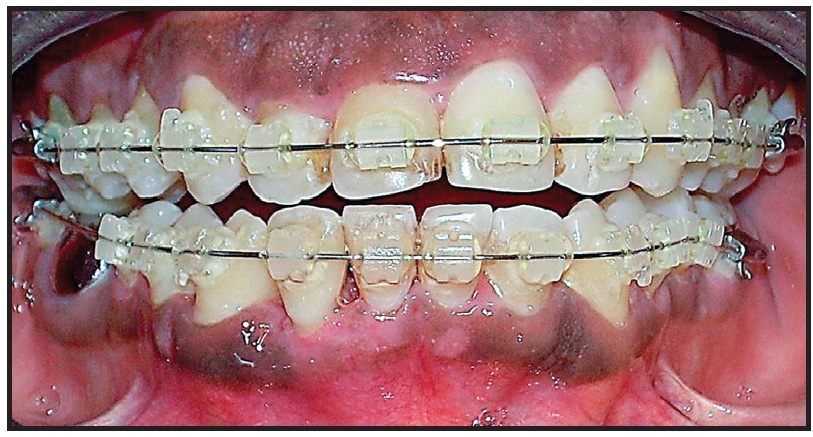

After an initial phase of dental scaling and polishing, orthodontic treatment began with .022" Roth-prescription brackets in both arches (Fig. 2).

Fig. 2 Initial bracket placement, with glass-ionomer-cement bite plane bonded to occlusal surfaces of upper first molars to unlock traumatogenic occlusion.

To unlock the occlusion, glass-ionomer-cement bite planes were bonded to the occlusal surfaces of the upper first molars. The archwire series consisted of flexible .016", .018", and .020" round coaxial wires, followed by preformed .016" and .018" round stainless steel wires. After five months of treatment, the mobility of the lower right lateral incisor persisted, despite the elimination of the traumatic occlusion (Fig. 3). Periodontal probing of the tooth's labial root surface revealed EIRR, which was confirmed with an occlusal radiograph (Fig. 4).